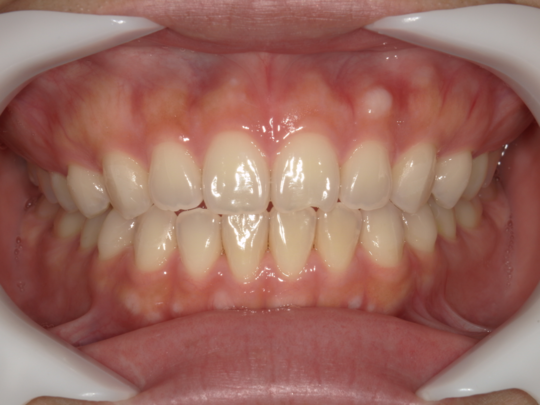

治療後

治療の副作用(リスク)歯の動き方には個人差があり、予想された治療期間が延長する可能性があります。。マウスピースの使用状況、矯正歯科治療には患者さんの協力が必要であり、それらが治療結果や治療期間に影響します